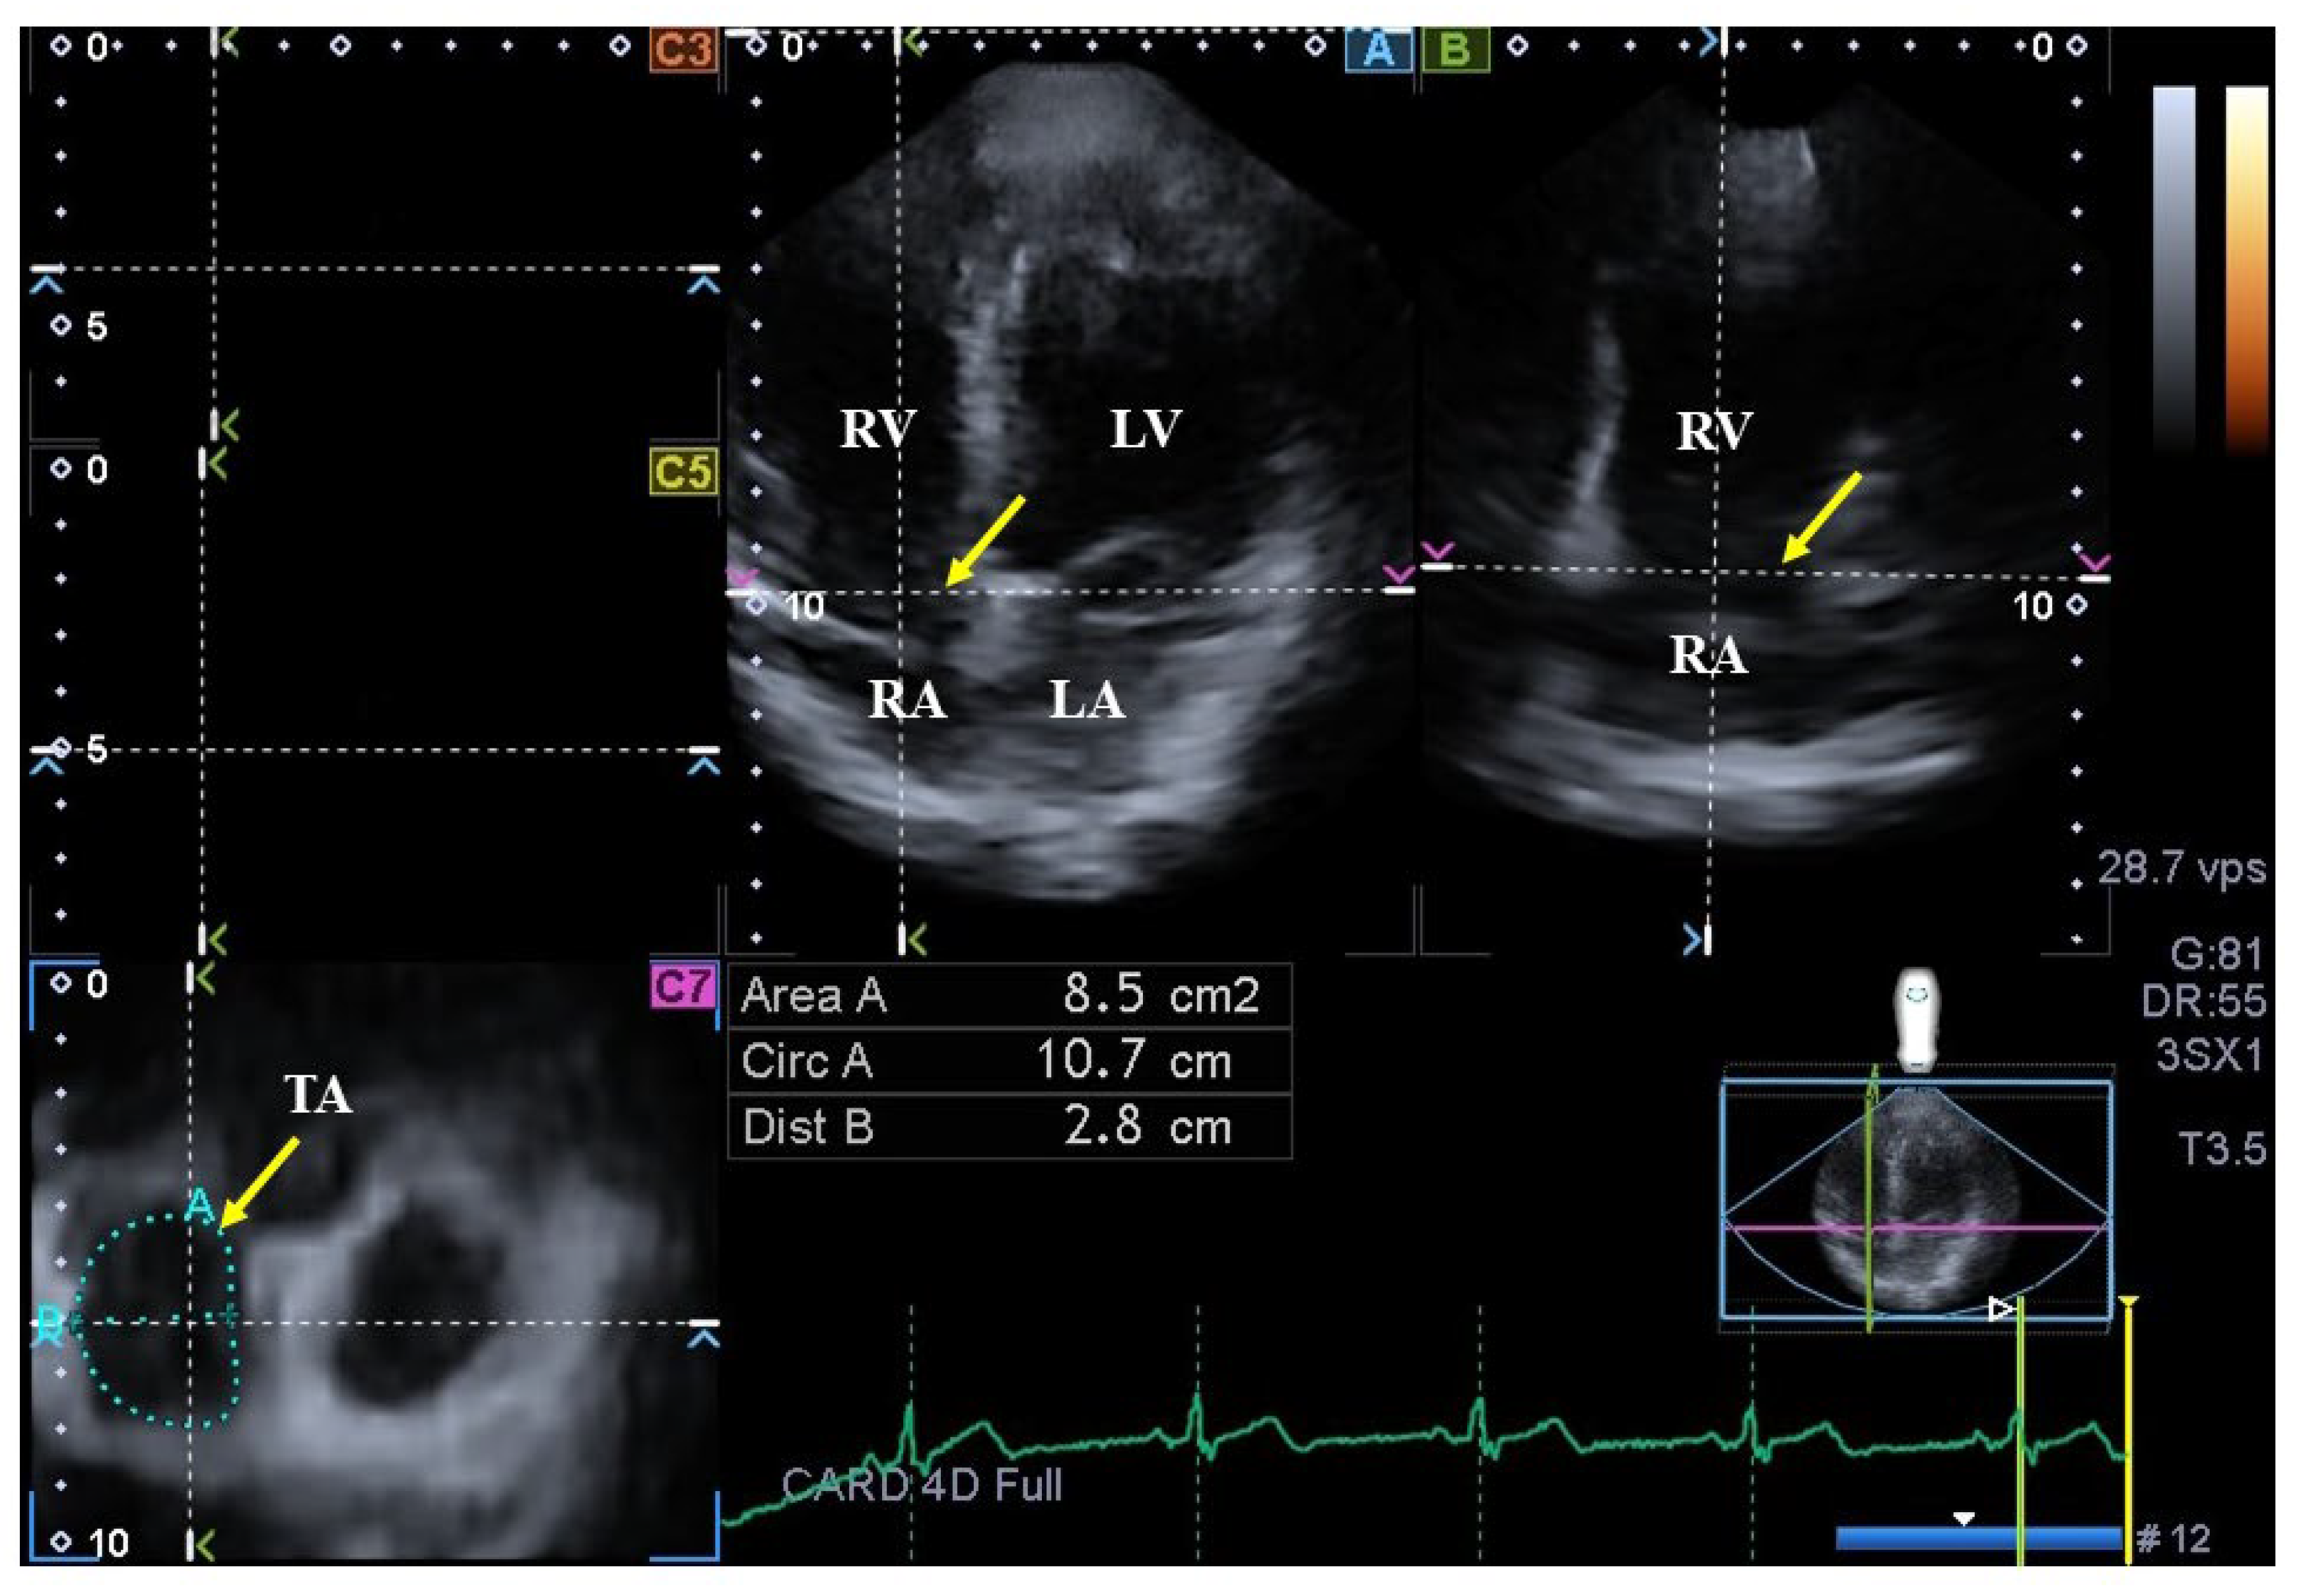

2.5. Quantification of 3DSTE-Derived TA Dimensions